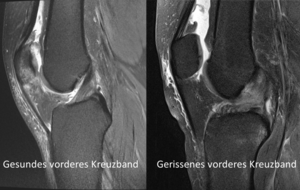

Wenn eines der zwei Kreuzbänder teilweise oder vollständig gerissen ist, spricht man von einem sogenannten Kreuzbandriss oder einer Kreuzbandruptur. In den meisten Fällen ist bei einem Kreuzbandriss das vordere Kreuzband betroffen. Es gibt jedoch auch Fälle in denen das hintere Kreuzband betroffen ist.

Die Ruptur des vorderen Kreuzbands (VKB), ist sehr viel häufiger als ein Riss des hinteren Kreuzbandes (HKB). Oftmals treten Kreuzbandrisse auch nicht isoliert, sondern im Zusammenhang mit komplexeren Verletzungen auf. So können bei einem Kreuzbandriss unter anderem der Meniskus oder die Außen- beziehungsweise Innenbänder ebenso verletzt sein.

Ein Kreuzbandriss muss medizinisch von einem Spezialisten untersucht werden. Aufgrund der Diagnose kann ein Kreuzbandriss konservativ (ohne Operation) oder operativ behandelt werden.